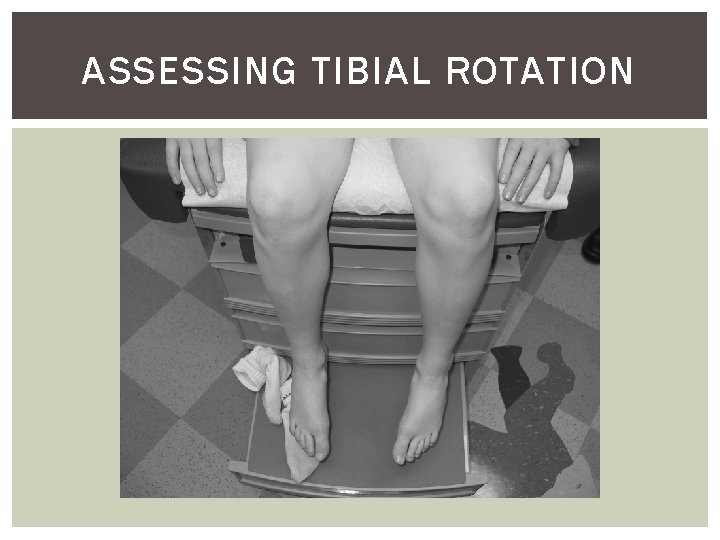

ASSESSING TIBIAL ROTATION